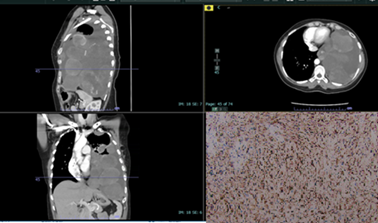

Figure

1:

CT Chest in sagittal (upper left), axial (upper right) and coronal views

(bottom left) showing a large loculated left pleural effusion containing

multiple enhancing pleural-based masses. This is an ill-defined, partially

calcified 8.9 x 5.8 cm pleural-based mass (red arrow) and a homogeneously

enhancing mass more superiorly (blue arrow) in the pleural space measuring 8.8

x 5.8 cm were noted. Numerous additional morphologically similar masses are

present involving the left mediastinal, costal and diaphragmatic pleural

surfaces (green arrow). The bottom right image shows strong MUC 4 positive

staining (black arrow) on the biopsy specimen, confirming low-grade fibromyxoid

sarcoma.

MUC4 (Figure 1). A diagnosis of